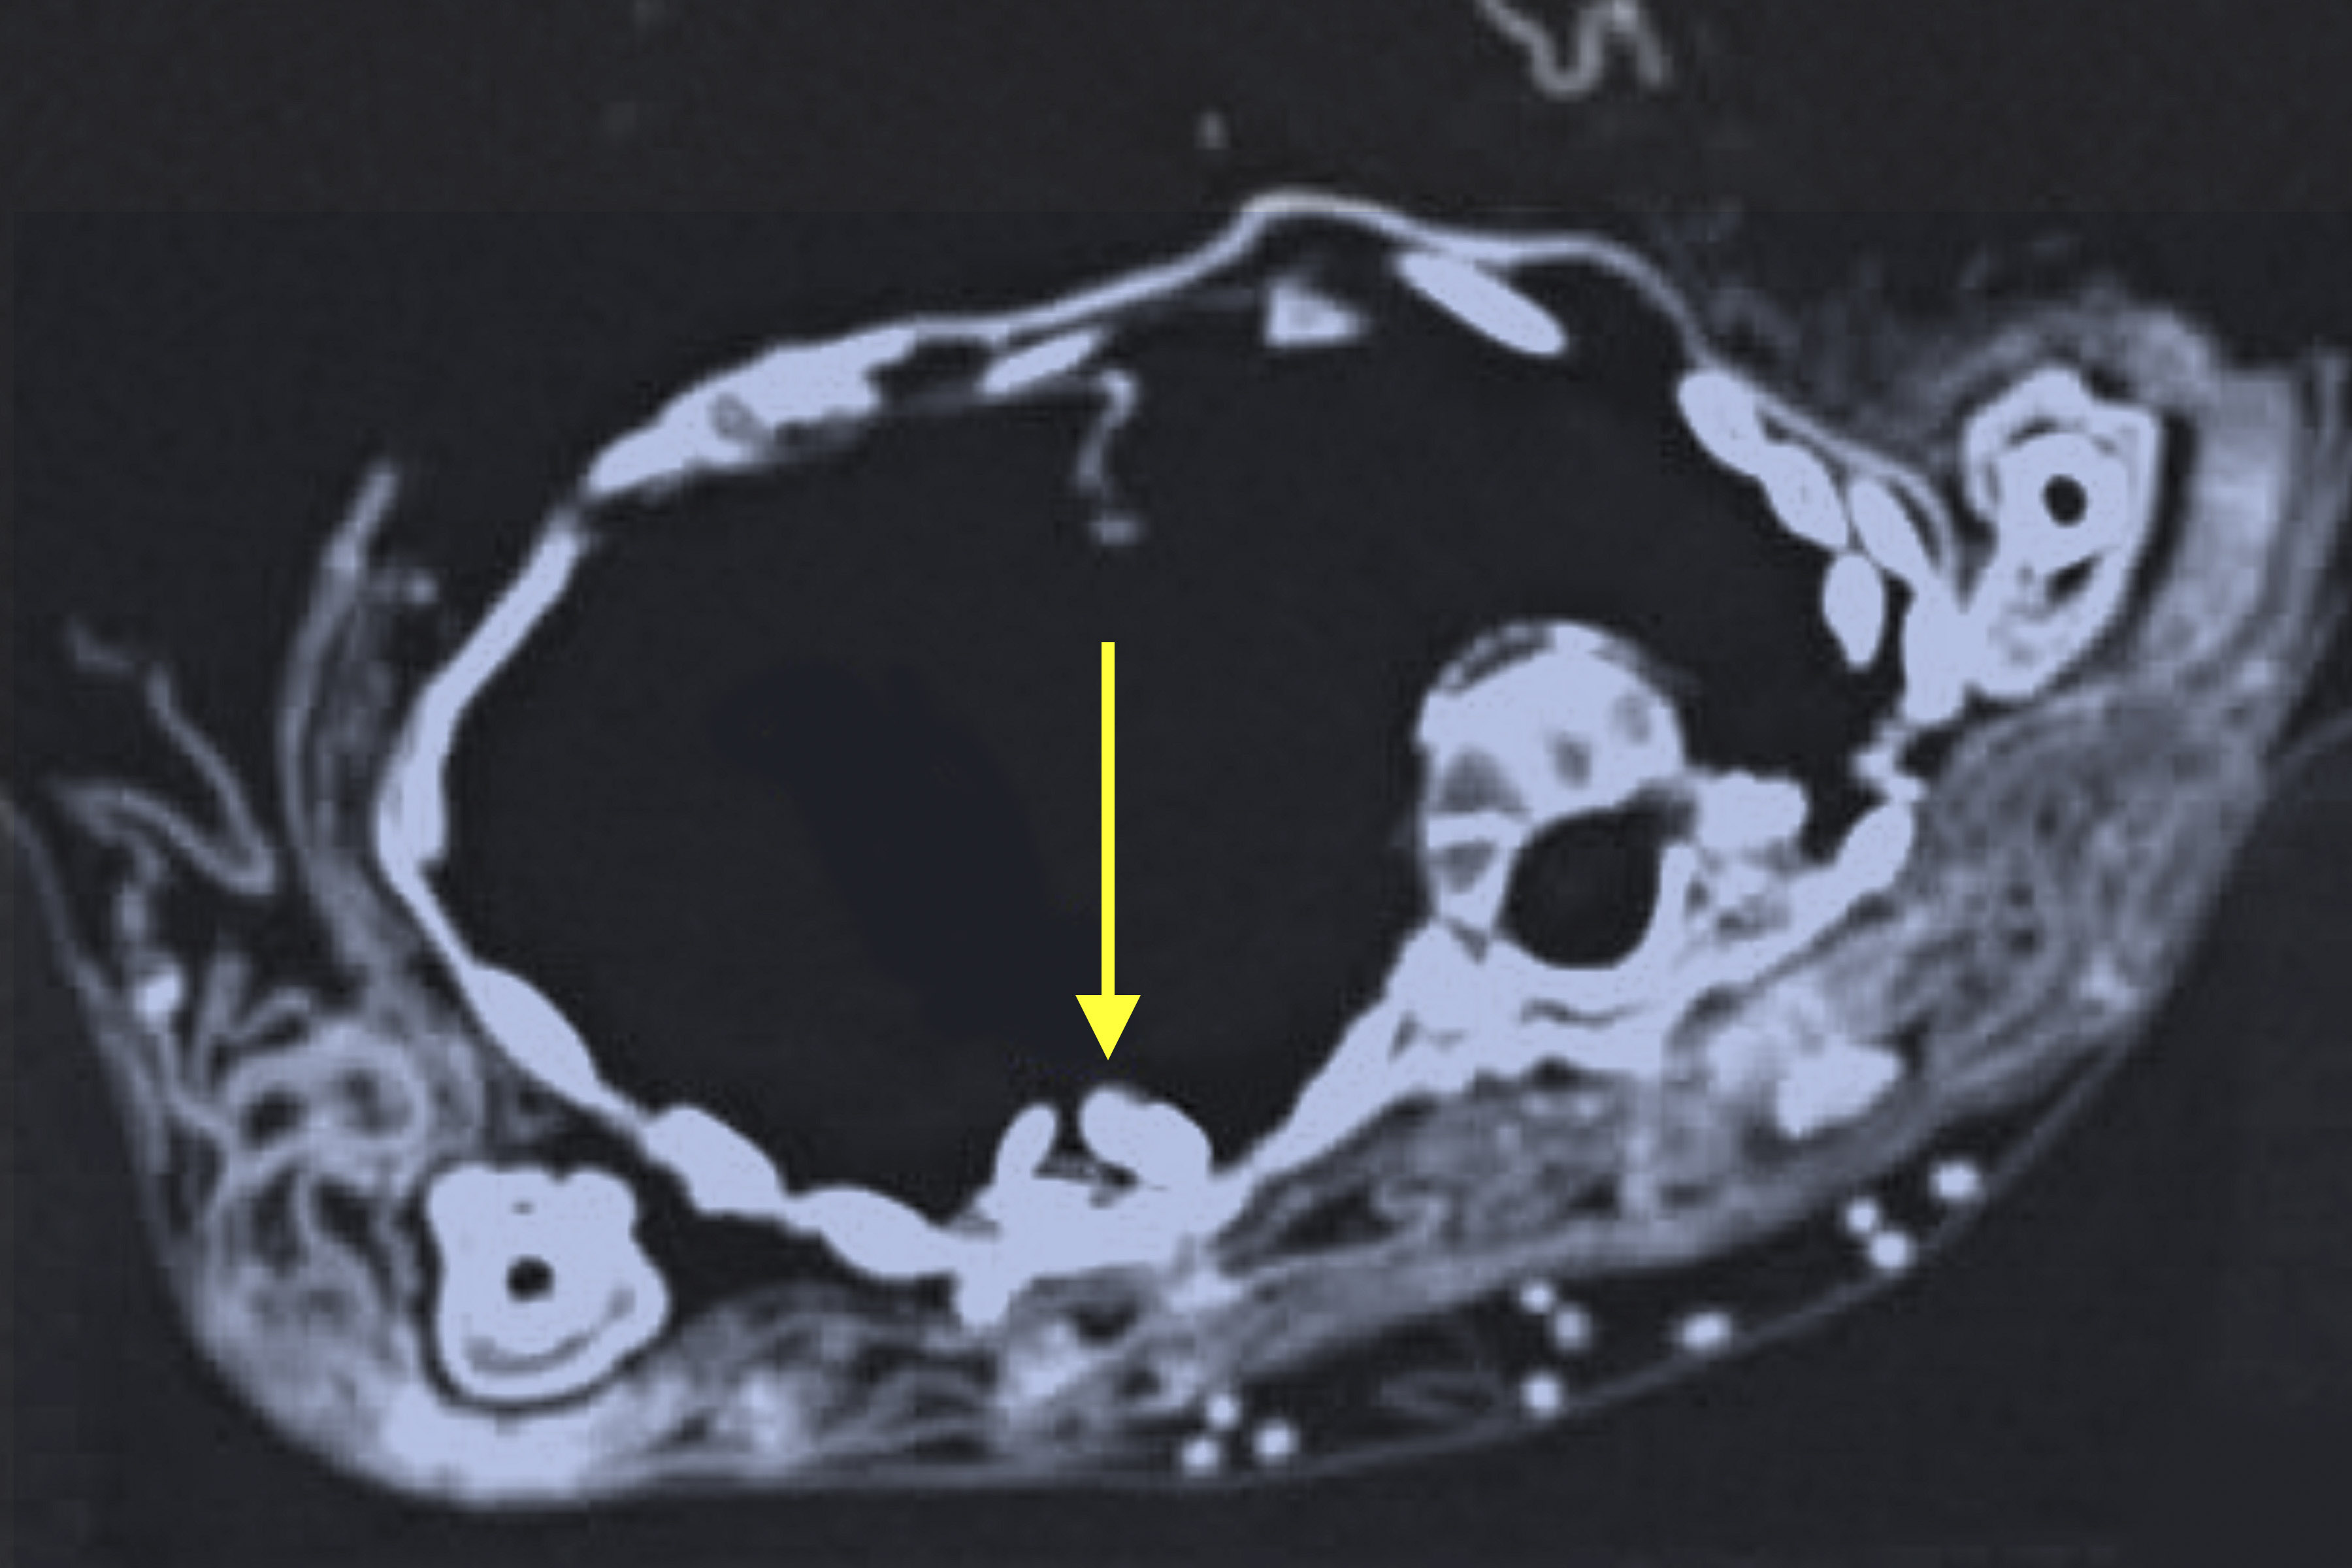

A previous scan performed at the School of Medicine about 10 years ago showed four amulets, or fragments of amulets, nestled deep within the wrappings, but with the technology at that time, it was impossible to see whether they bore any patterns or symbols.

The new scan of the child mummy took only a minute, and researchers from the Science Center and the School of Medicine crowded around computer monitors to see the initial results. To everyone’s surprise, a fifth amulet – possibly a heart scarab amulet – was visible inside the chest cavity near where the heart once was. It was too early to say whether it had been placed inside the baby’s chest deliberately or had fallen into the body over the centuries. The team expects to learn more about the amulets and the skeleton as they study the images.